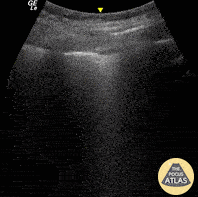

Pulmonary - Pleural Shred Sign

Seen here is a pleural shred sign (discontinuity of a thickened pleura) and B-lines. Images were acquired from the LLL BLUE point on a patient who presented with fever and purulent discharge from tracheostomy site; all findings consistent with diagnosis of pneumonia. Renato Melo, Emergency physician, H.C. de MarĂ­lia-SP, Brazil @Renato_Melo_